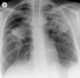

Progressive massive fibrosis (PMF), characterized by the development of large conglomerate masses of dense fibrosis (usually in the upper lung zones), can complicate silicosis and coal worker's pneumoconiosis. Conglomerate masses may also occur in other pneumoconioses, such as talcosis, berylliosis (CBD), kaolin pneumoconiosis, and pneumoconiosis from carbon compounds, such as carbon black, graphite, and oil shale. [Source: Wikipedia ]